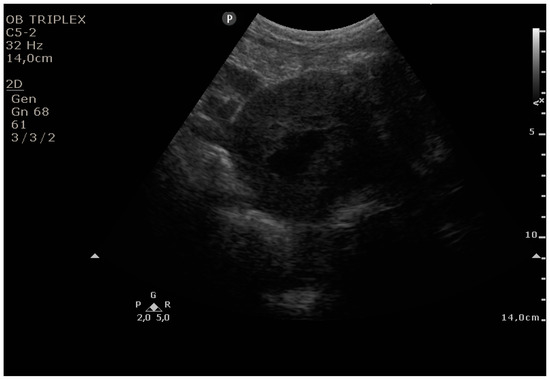

The PUUS method evaluates the proportion of the endometrial length occupied by blood or debris, as follows (Figure 1, Figure 2, Figure 3, Figure 4 and Figure 5):

Grade 0: no blood or debris in the uterine cavity;

Figure 1. Grade 0: no blood or debris in the uterine cavity.